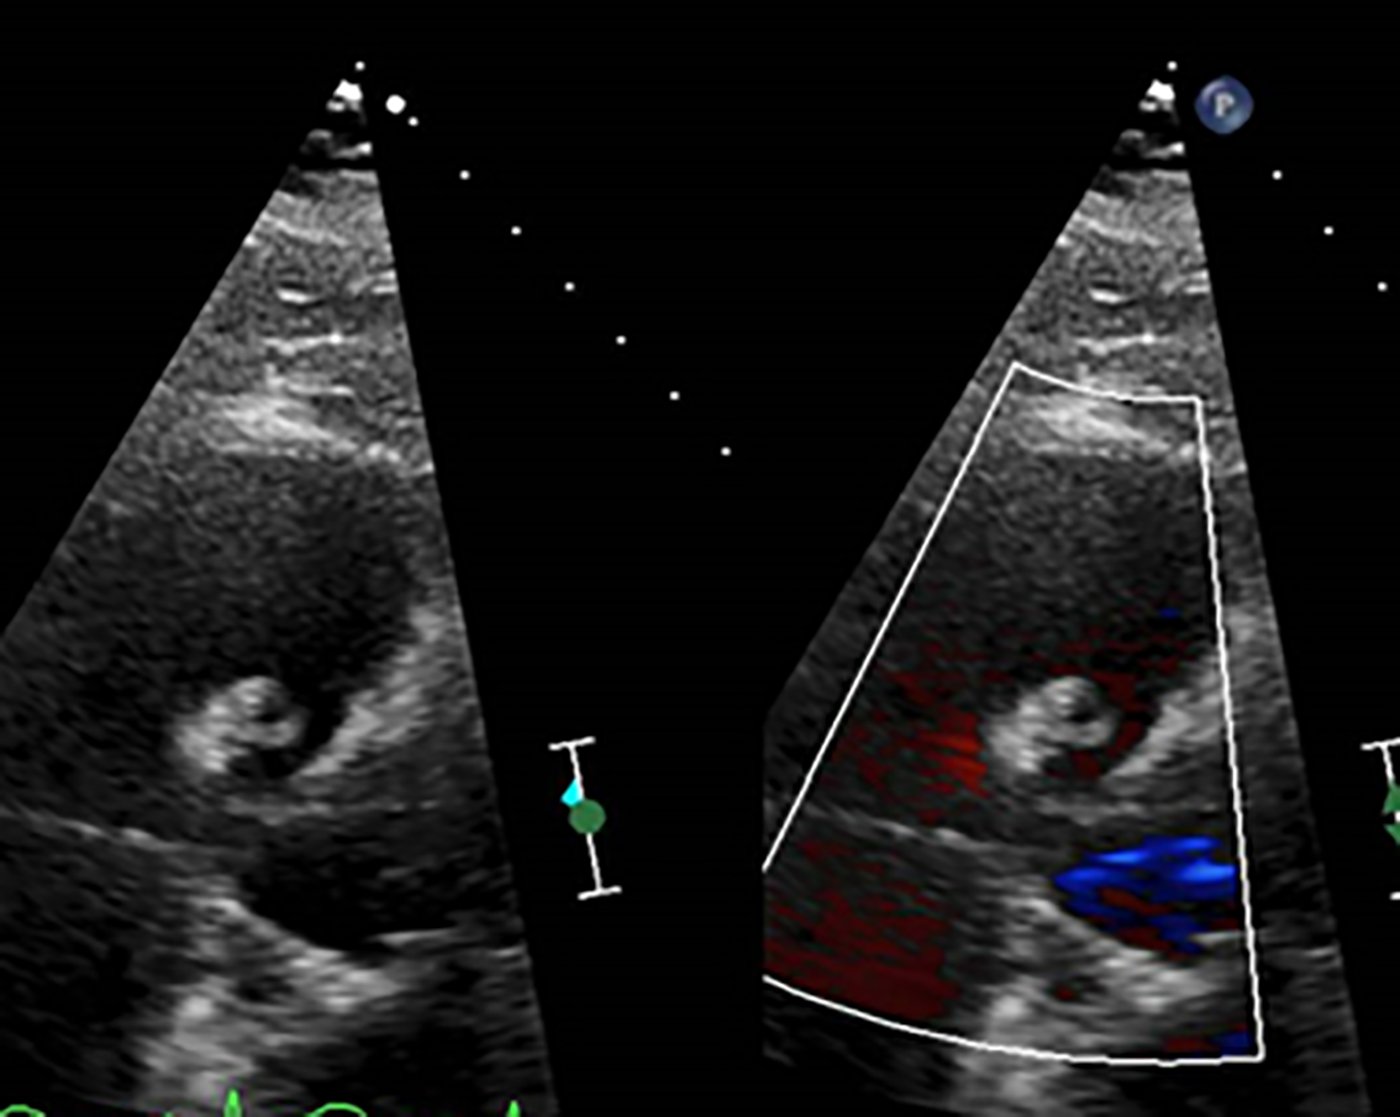

Endovascular coil embolization continues to become a more frequent modality of addressing hemorrhage and bleeding in patients. Migration refers to the coil unraveling or moving from the original embolization site. Migration of a coil is a known complication which can lead to serious consequences based on where the coil migrates. Despite increasing efforts to improve safety and technique, the risk of migration remains. We present a case of an embolization coil that migrated to the right ventricle, which was incidentally found roughly 2 months after undergoing an interventional radiology procedure for gastric variceal bleeding. The patient presented to the emergency department with dyspnea and abdominal pain. Unique images were obtained during his visit and in subsequent follow-up. As use of vascular embolization coils continues to become more commonplace, understanding the risks and complications of these procedures remains an important aspect of providing care for patients once they have left the interventional radiology suite. Coil migration should be a differential to consider in patients who present to the emergency department with signs or symptoms of arrhythmia or pulmonary embolism who have undergone a coil embolization procedure.